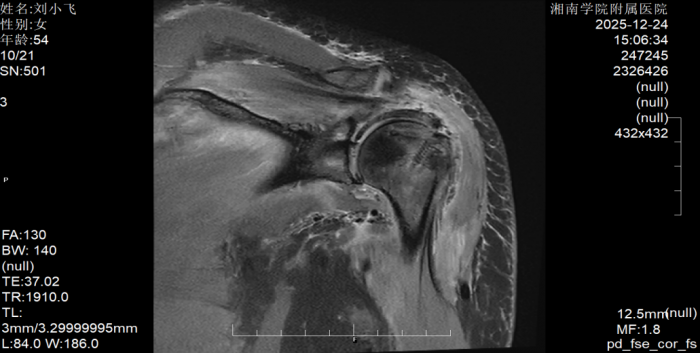

据了解,患者刘阿姨因左肩部疼痛辗转求医多日,尝试吃药、针灸、推拿等多种治疗后症状不仅未改善,反而持续加重,最终发展到无法端碗吃饭、自行穿衣洗澡的程度。转诊至湘南学院附属医院后,经术前MRI检查确诊为巨大肩袖撕裂,且肩袖缺损范围大、肌腱质量差,传统修复方式难以达到理想效果。